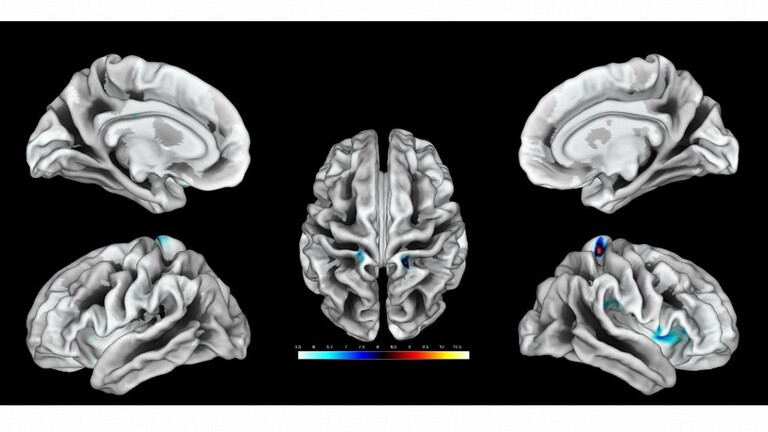

راما دياب – البلاد حالة ترتبط بنمو الدماغ وتؤثر على كيفية تمييز الشخص للآخرين والتعامل معهم على المستوى الاجتماعي مما يتسبب في حدوث مشكلات في التفاعل والتواصل الاجتماعي ويتضمن أنماط محدودة ومتكررة من السلوك في التفاعل الاجتماعي والتواصل إنه اضطراب…